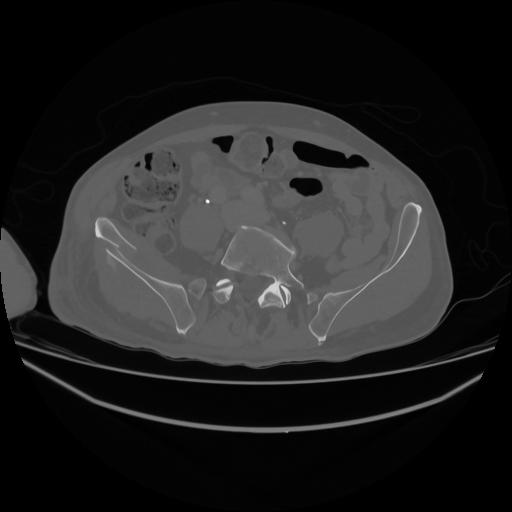

5 CUERPO,CE,Vol,1.0,CUERPO,,